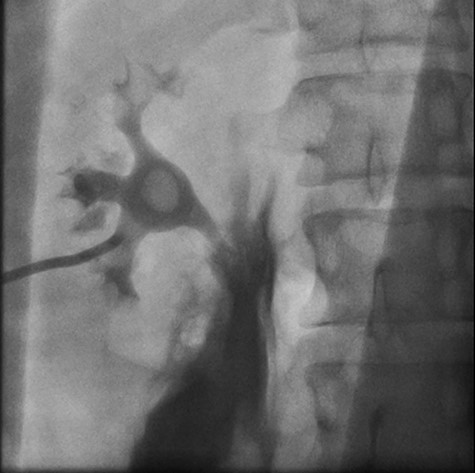

Right retrograde cystoscopy exhibiting extravasation of contrast.

Cystoscopy with retrograde pyelogram was performed by the urology team and this showed total disruption of the UPJ bilaterally with extravasation of contrast (Figs 3 and 4). She underwent bilateral interventional radiology nephrostomy tube placement. The definitive repair was planned for after pregnancy, but she required tube changes every 6 weeks. There was no fetal distress during her stay. She recovered well and was discharged after 5 days.